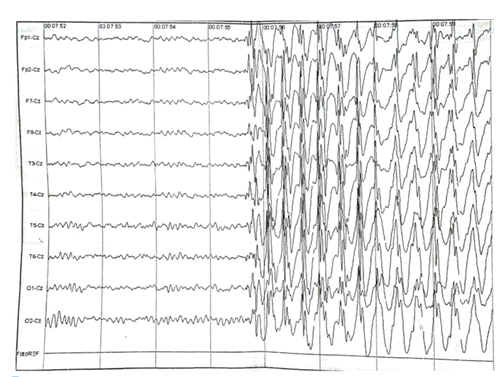

At the age of 12, her mother related episodes as “blackouts” where the patient did not answer her. The mother took the patient to a Psychologist which said, after some sessions, the family should take the patient to a Neurologist. After doing an ECG (Figure 1) with photostimulation and hyperpnea, as requested by the Doctor, she was diagnosed with AS and started taking Sodium Divalproex.

Figure 1 Eletroencephalogram of the brain.